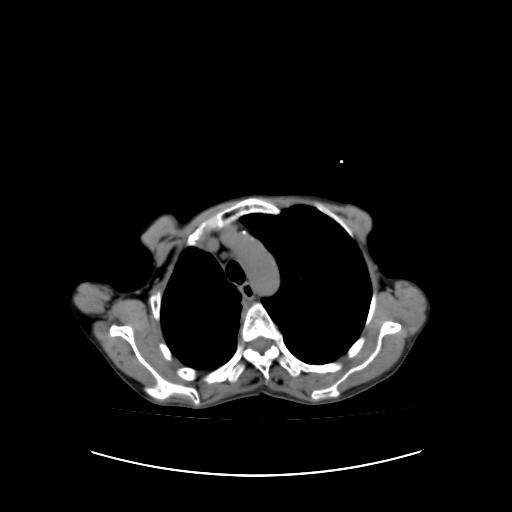

标题: CT16930:女 59 胸痛6个月 胸水脱落细胞学见瘤细胞 [打印本页]

标题: CT16930:女 59 胸痛6个月 胸水脱落细胞学见瘤细胞

右侧胸膜增厚,局部呈结节状增厚,右侧胸腔少量积液。双肺未见确切肿块影。纵隔未见淋巴结肿大。气管、支气管通畅。考虑右侧胸膜间皮瘤(恶性?)可能性大。不除外癌性胸膜炎。

右侧胸廓塌陷,右侧胸膜广泛增厚并见多发胸膜结节,右侧少量胸腔积液并包裹。

右侧广泛胸膜增厚,局部呈结节状增厚,右侧胸腔少量积液。双肺未见确切肿块影。纵隔未见淋巴结肿大。气管、支气管通畅。考虑右侧胸膜间皮瘤(恶性?)可能性大。支持!

胸膜转移瘤  包裹性胸腔积液  肺内转移

右胸腔结节均考虑来自胸膜(部分来源于叶裂),考虑胸膜间皮瘤或转移瘤.